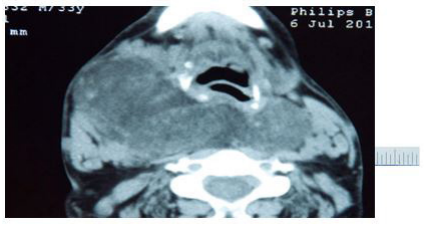

| Figure 1: A Computed tomography of the neck showing enlargement depending on the thyroid lodge and compressed the trachea |

In laboratory data, T4: 1.05 ng/dL (N: 0.90–1.5 ng/dL), TSH: 0.534 mIU/mL (N: 0.3–5, 5 mIU/mL), and thyroid auto-antibodies such as Anti-TPO (antithyroid peroxidase) and anti-Tg (antithyroglobulin) were found to be negative. Other laboratory findings were WBC: 6000, Hb: 8.6 g/DL, Hct: 25.4%, MCV: 82.2 fL, Plt: 190000 𝜇L, urea: 70md/dL , creatinine: 3mg/dL , fasting blood sugar :90 mg/dl, C-reactive protein(CRP):8.9 mg/dL and hepatic function tests were found to be normal. Thyroid ultrasound showed hypertrophy of the entire thyroid gland, isoechoic and no identifiable nodules. A CT scan of the neck and chest showed hypertrophy of the thyroid with decreased density and asymmetrical growth, more pronounced in the right lobe. Retropharyngeal extension and the airway was engulfed, displaced, and molded.

Both lobes had similar histological characteristics, with total loss of normal architecture, few thyroid follicles, often dilated bordered by regular thyrocytes without any atypia , thyroid follicles surrounded by large amorphous ranges, non-cellular material and eosinophilic, which has also been seen in vascular walls. This stained material with Congo red procedure, showing greenish birefringency under polarized light .Upon immunohistochemical evaluation, these amyloid deposits were positive for AA .There was no immunoreactivity noted for calcitonin, thereby excluding MTC. The final diagnosis was consistent with AG (Figures 1,2,3,4 & 5).